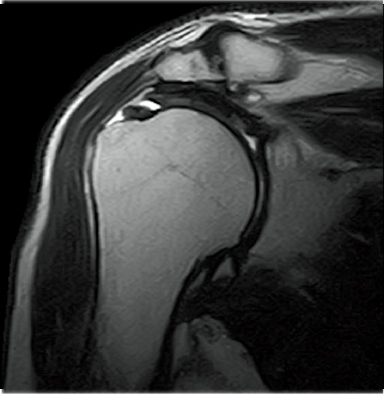

FatSat-PDWI